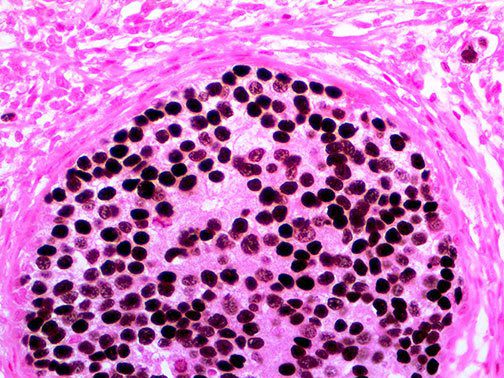

It is the ICU physician who is most likely to witness one of the deadliest manifestations of the abnormal immunological response, the cytokine storm syndrome (CSS). This response is also referred to by some as the cytokine release syndrome (CRS). CSS is characterized by continuous activation and expansion of macrophage and lymphocyte populations, which secrete large amounts of cytokines, causing the cytokine storm. This massive cytokine release is akin to hemophagocytic lymphohistiocytosis (HLH) disease, a syndrome characterized by initial unchecked and persistent activation of cytotoxic T lymphocytes and NK cells.

Clinical and laboratory manifestations of HLH include fever, enlarged liver and/or spleen, neurologic dysfunction, coagulopathy, liver dysfunction, cytopenias (i.e., low levels of erythrocytes, leukocytes, and/or platelets), hypertriglyceridemia, hyperferritinemia, hemophagocytosis, and eventually diminished NK cell activity as the immune system becomes progressively paralyzed. HLH can be familial (primary HLH) or secondary to another disease process (sHLH), such as rheumatic disease, in which it is referred to as macrophage activation syndrome (MAS, characterized by elevated ferritin).